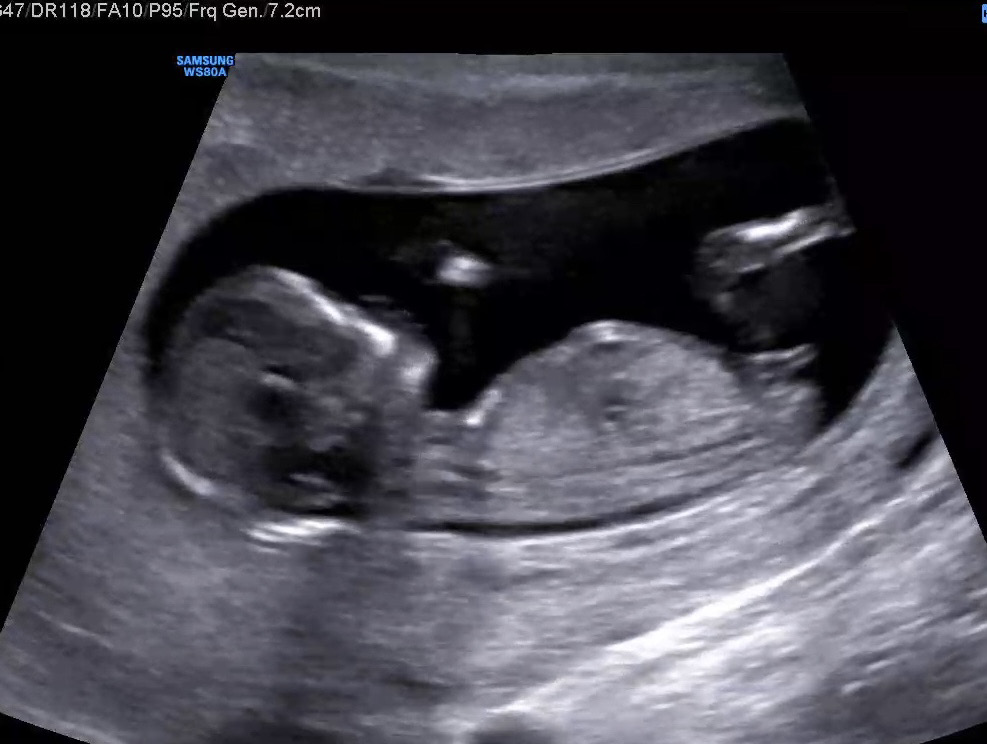

성별 참견 부탁드려요 😇👼

아래길쭉한 부분을 보면 되는건지 긴가민가하네요ㅠ